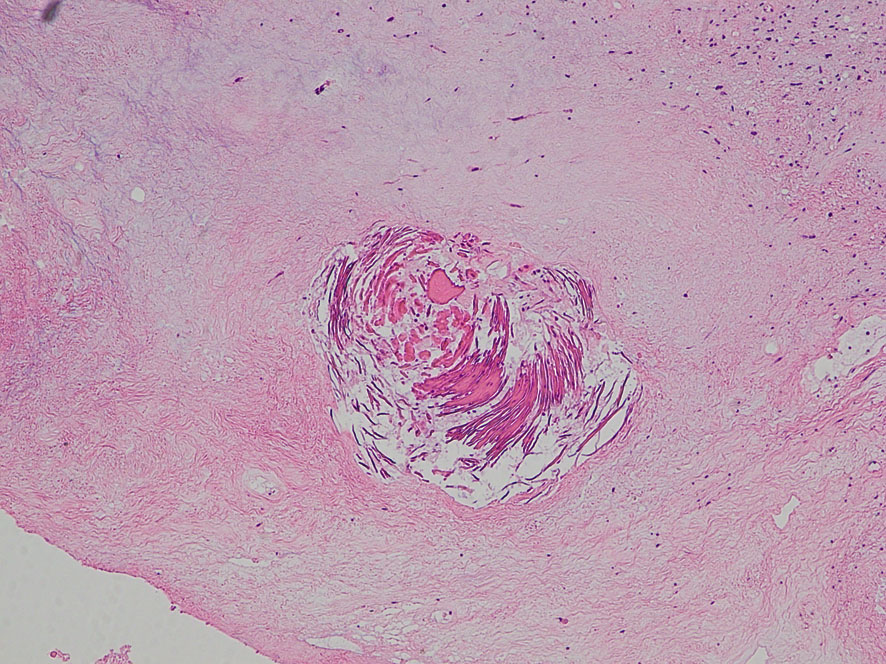

照射後の奇形腫の病理像

左上にはcartilage,右上にはkeratin squamous tissueがみられます。左下は繊維生組織のみdense collagenous tissueです。

生検術で胎児性癌と未熟奇形腫の混合型と診断されたために,化学療法と61.1グレイの放射線治療がなされていました。しかし,大きな松果体腫瘍が残り全摘出したものです。この子の腫瘍は治っていて元気に暮らせています。

奇形腫の照射後はいつもそうなのですが,dense collagenous tissueとfibroblastic spindle cellが組織の主体となっています。要するに肉芽腫のようなものです,ですから,手術摘出ではものすごく硬い線維性の腫瘍となっていてハサミでも切れずに難渋します。出血もしないし脳とは剥離できるのできます。放射線化学療法前の生検による組織像(悪性要素)は消失して単なる成熟奇形腫との病理診断となってしまいます。しかし,この組織のどこかに悪性度の高い細胞が潜んでいて,播種再発するなどということも経験しました。放射線治療後の病理組織診断はその後の予後の予想のためには役に立ちません。

左上の写真で見えるのは,腫瘍内部にあった小脳組織です。内胚葉,外胚葉性組織など多様に分化した組織が混入しています。